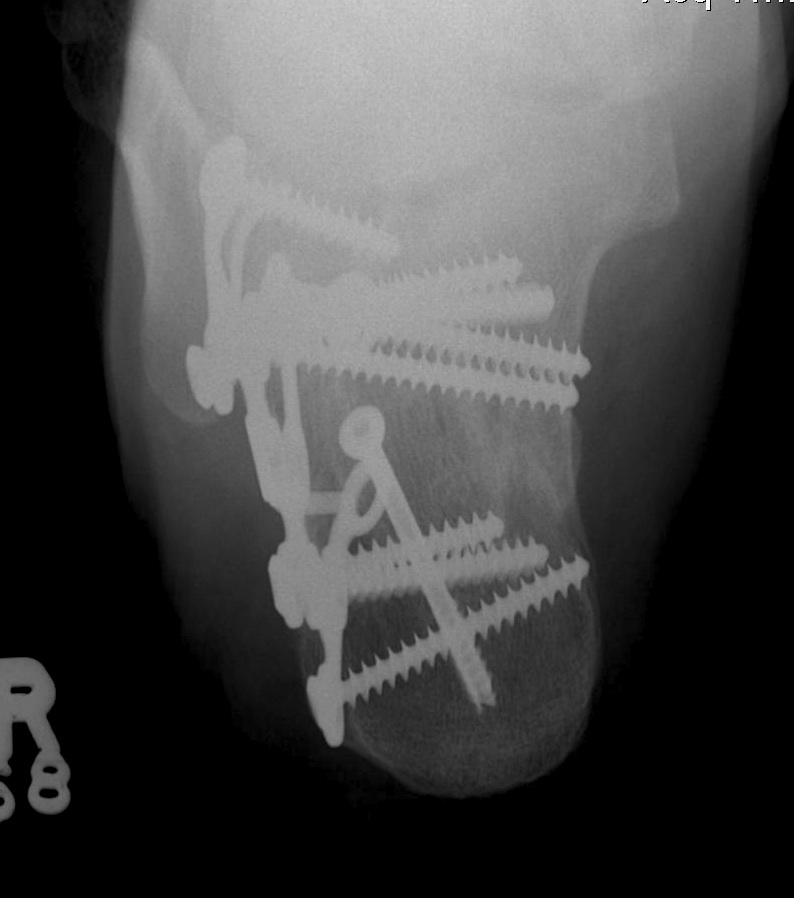

Calcaneal Malunion

Issues

Varus hindfoot - locks midfoot

Peroneal impingement

Shoewear problems

Options

Lateral wall exostectomy and peroneal tenolysis

Calcaneal osteotomy

STJ arthrodesis

Results

Farouk et al Foot Ankle Int 2019

- 18 varus calcaneal malunions

- combined subtalar joint fusion / calcaneal osteotomy / lateral wall exostectomy

- outcome score increased from 60 to 80